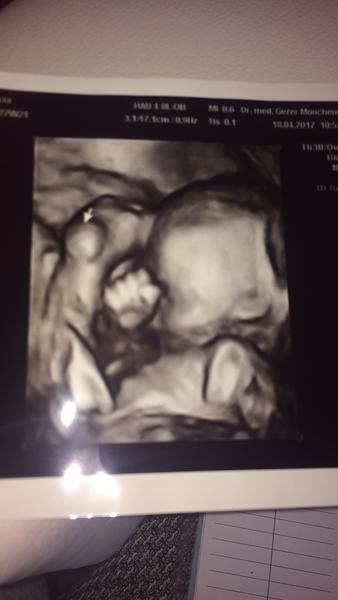

@lilianna1xs podla mňa váha super, ja som bola dnes som 30tt, váha 1590g.

@lilianna1xs krásna fotka, mna potešila, ruky nohy lietajú kde kade 🙂

@lilianna1xs krasna bambulka. Len tak so srandy som kukla jednu tabulku tu na konikovi a podla nej by si mala byt v 31. tyzdni. Babatka v 27 tt maju v priemere 875g. Neotehotnela si mesiac skor nahodou? 🙂

@lilianna1xs vau tak vaha je tiez vacsia, mne povedal, ze vyzera byt babo na 28.tyzden a ma 1107g cize ako pise

@juliane126 to je akoby az okolo 30.-31.tyzdna...ja sa uz tesim opat na 3D v 30.tyzdni...pritom som bola proti 3D, ze zbytocne nedam presviecovat babo 🙂 a teraz sa uz neviem dockat ked ho uvidim